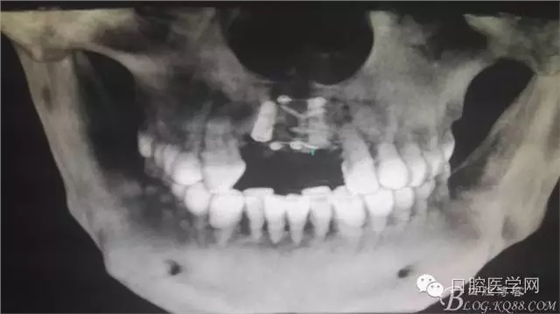

為他院轉(zhuǎn)診患者。男,無(wú)吸煙史,前牙因齲壞治療后,外力折斷導(dǎo)致拔除?,F(xiàn)拔除該牙后兩個(gè)多月。 左上區(qū)域骨寬度不足,計(jì)劃植入種植體同期GBR。

左上區(qū)域骨寬度不足,計(jì)劃植入種植體同期GBR。